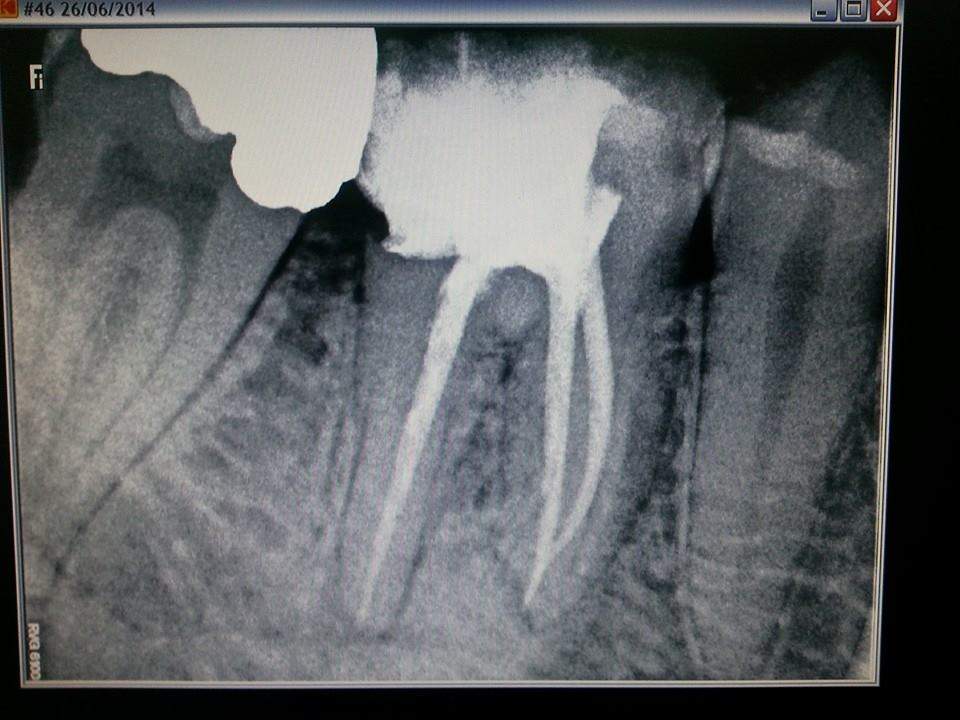

Primjeri korektno endodontski tretiranih zuba u našoj ordinaciji